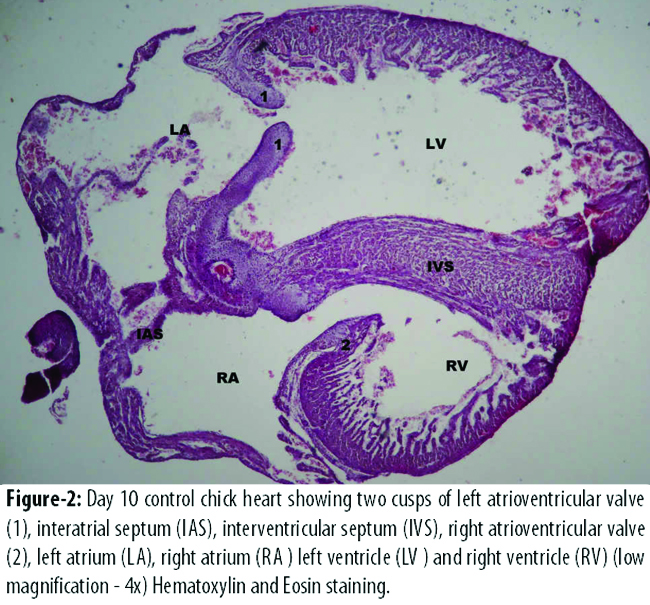

The diameter of left atrial and left ventricular cavity was more in B2 than that of A2 (Figure-2).

However, the difference was not statistically significant. The diameter of right atrial and right ventricular cavity was significantly more in B2 than that of control group A2 (Table-3).

The diameter of left atrial and left ventricular cavity was more in experimental group B2 than that of control group A2, but, the difference was not statistically significant. The diameter of right atrial and right ventricular cavity was significantly more in experimental group B2 than that of control group A2. These findings were similar to the findings seen at day 7. The diameter of all the cavities was more in the day 10 experimental group than that of day 10 control group, presenting a form of dilated cardiomyopathy due to alcohol. Alcoholic cardiomyopathy accounts for 33% of all dilated cardiomyopathies. It is manifested by cardiomegaly, cardiac hypertrophy, compromised ventricular contractility and cardiac output.16 In another study done by Cheng et al, it was seen that chronic alcohol consumption causes inhibition of myocyte contraction and relaxation and dysfunctional calcium regulation leading to the development of alcoholic cardiomyopathy.17